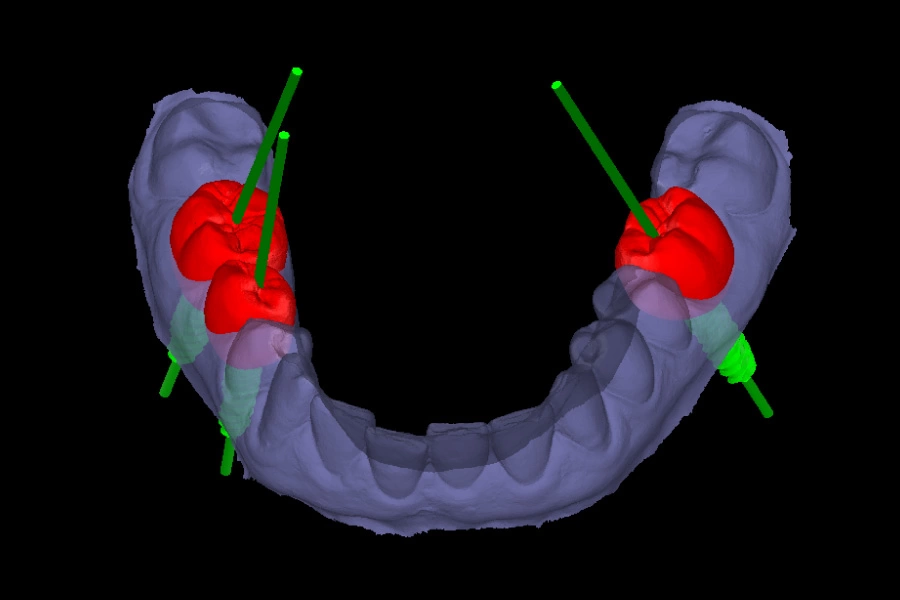

La planificación digital en implantología se basa en el análisis tridimensional de la anatomía del paciente mediante TAC o CBCT. Esto permite conocer con precisión la cantidad y calidad de hueso, la relación con estructuras anatómicas sensibles y el espacio protésico disponible.

Gracias a estos datos, es posible decidir con antelación la posición, el tamaño y la angulación del implante, así como anticipar posibles limitaciones o riesgos. Este enfoque reduce la improvisación y aumenta la previsibilidad del tratamiento.

Además, la planificación digital facilita una visión global del caso antes de la cirugía. Permite simular diferentes escenarios terapéuticos, comparar alternativas y elegir la opción más segura y conservadora para el paciente. También mejora la comunicación clínica, ya que ayuda a explicar el tratamiento de forma visual y comprensible, reforzando la toma de decisiones informadas y realistas.